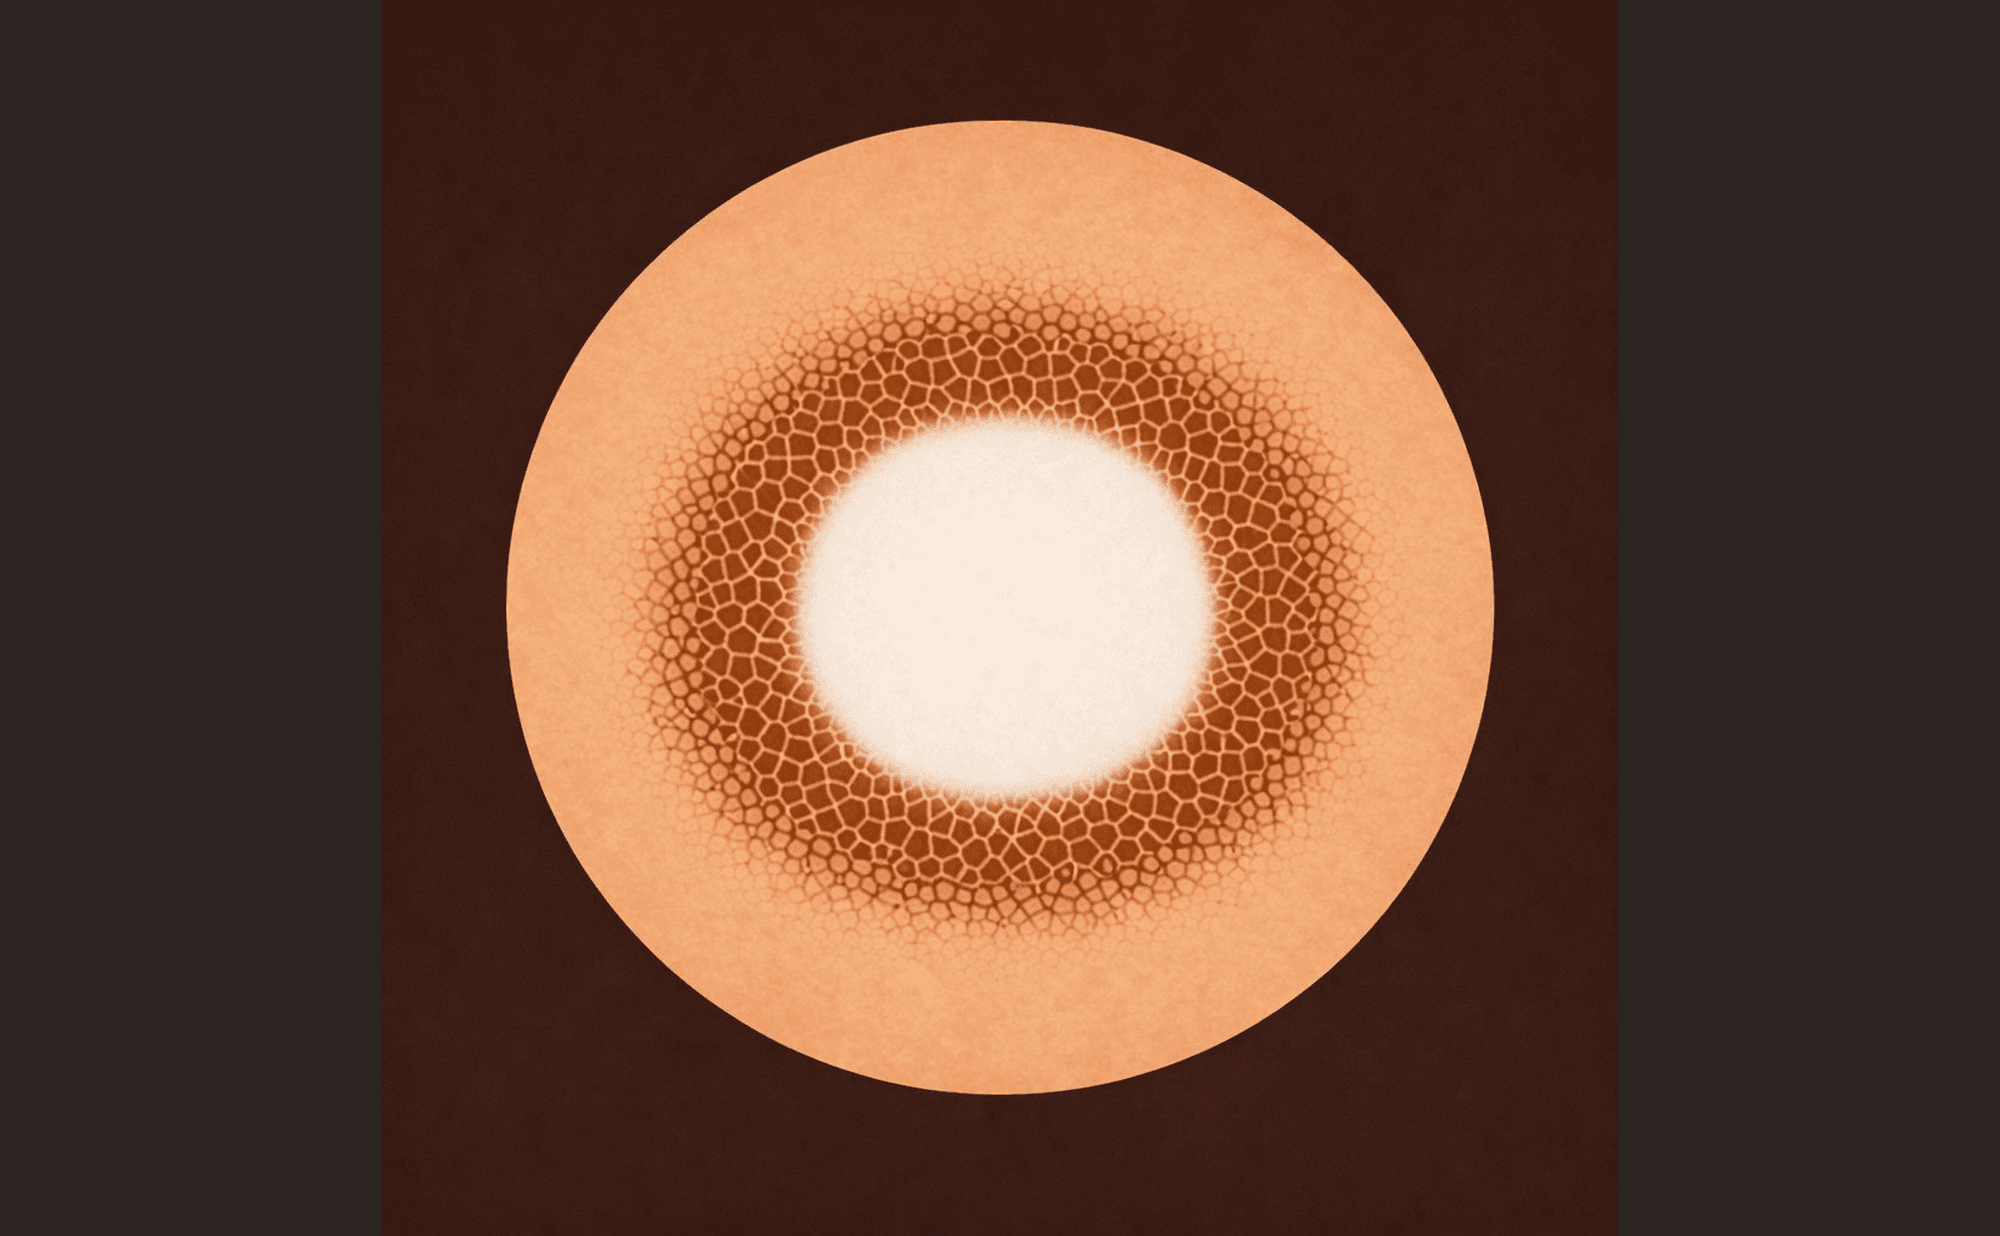

Classic dermatofibroma: central white patch with peripheral pigment network — the bullseye pattern

The combination of these two features — central white patch surrounded by peripheral pigment network — is highly characteristic. It creates a target-like or bullseye pattern: white centre, brown ring, fading edges.